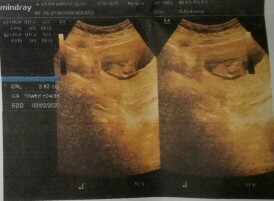

9w 5d